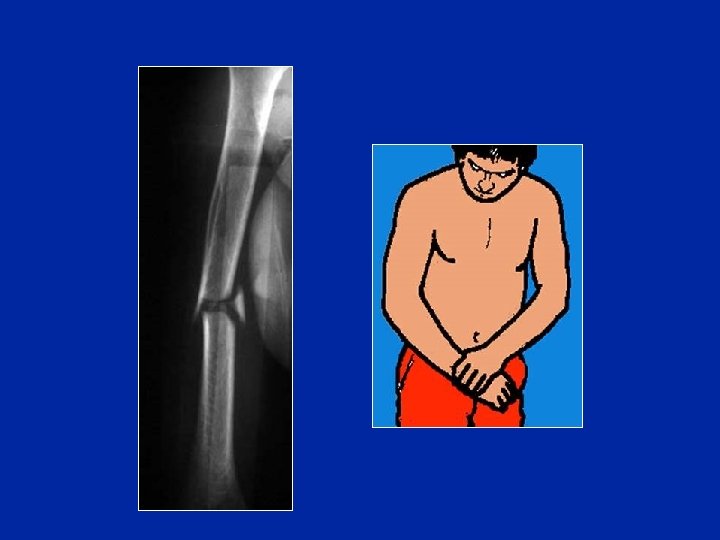

La déformation est parfois évidente De profil, il y a une angulation antérieure